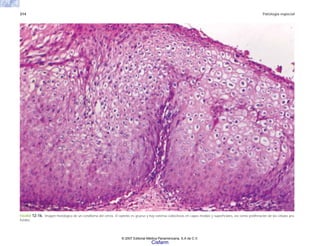

FIGURA 2-5. Histología de la piel en la esclerodermia, con abundante colágena por debajo del nivel de

las glándulas sudoríparas.